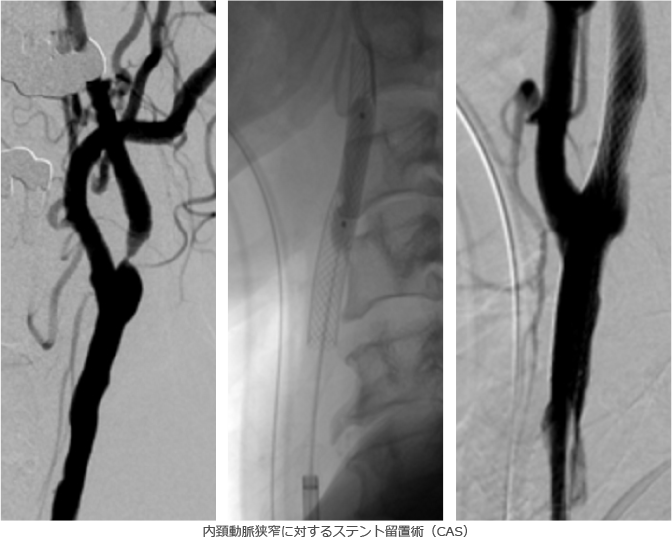

脳梗塞の治療に関しては、従来は脳梗塞の拡大・悪化を抑える点滴・内服とリハビリテーションによる機能回復が一般的でしたが、最近では発症後早期なら使用可能なt-PA療法(血栓を強力に溶かす点滴)や、カテーテルによる血栓回収・再開通療法が大きな効果を発揮するようになってきており、当院では24時間対応しております。また、内頚動脈狭窄症など脳梗塞の原因となりうる病変に対して行われる頸動脈ステント留置術(CAS)や、血管の慢性閉塞によって血流が足りなくなった部分に血流を補うバイパス手術などの治療も積極的に行っております。